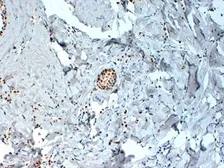

Description Mouse MonoclonalApplications WB ICC/IF IHC-P IHC-Fr FCM Dot ChIP assay IHC-P (cell pellet)Reactivity Hu, Ms, MkSummary Strong Erb staining in epithelial cell nuclei. Occasional weak to moderate staining is seen in surrounding stromal and endothelial cell nuclei. Sporadic light cytoplasmic staining is sometimes observed. We have also successfully detected ERb in colon and ovarian tumors using the same antibody.